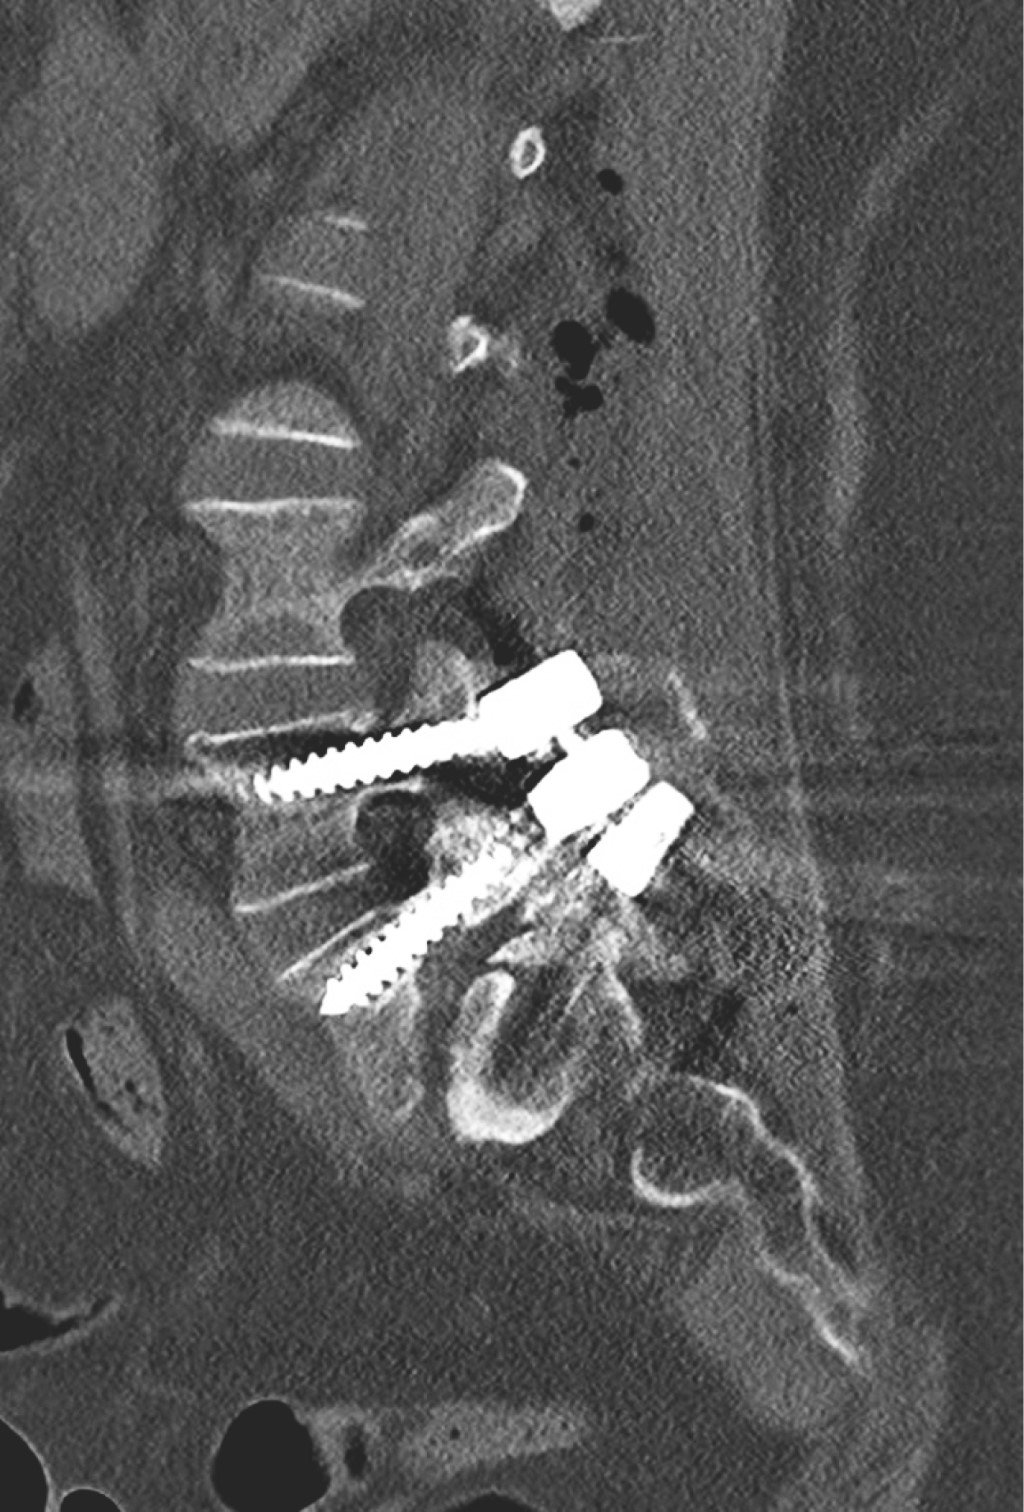

Ozone is a medical gas described since the 19th century; the ozone therapy has evolved to date in terms of its applications and its usefulness in various diseases due to its action at the molecular level and in dissimilar diseases associated with painful processes of inflammatory origin such as present in herniated discs of the spine, although the benefits of its application are currently in controversy, as well as the various complications that may occur after its application. Pneumocephalus is a complication that occurs in the background of a head injury or neurosurgery. Ozone infiltrations are used for the treatment of disc prolapse to reduce clinical symptoms. The anti-inflammatory effect of ozone is supported by its ability to oxidize compounds that contain double bonds such as arachidonic acid and prostaglandins, which are active substances with high concentrations in the inflammatory process. The appearance of pneumoencephalus and arachnoiditis chemical after epidural injection and also with ozone infiltrations is a rare complication but it has been described in recent years as a devastating post-application complication. Arachnoiditis can present as sensory and motor deficits, paresthesias, transient radicular neurological syndrome (TRNS), cauda equina syndrome, and conus medullaris. In relation to arachnoiditis, cases as severe as cauda equina syndrome after spinal anaesthesia, and more benign such as TSNR have been described, characterized by low back pain that radiates to the lower extremities, and not associated with motor deficits. neither sensitive, nor sphincter incontinence, which appears in the first 24 hours, which can last several days, and which resolves without neurological sequelae. Understanding the pathophysiology is important to assess and diagnose this type of neurological complications, especially in patients with disc disease who have undergone this type of treatment. The purpose of this report is to present the case of a patient with disc disease with the presence of radiculopathy who underwent infiltration by ozone therapy, who immediately presented complications such as pneumoencephalus and chemical arachnoiditis that led her to remain hospitalized in intensive care and present cauda equina syndrome.REFERENCES